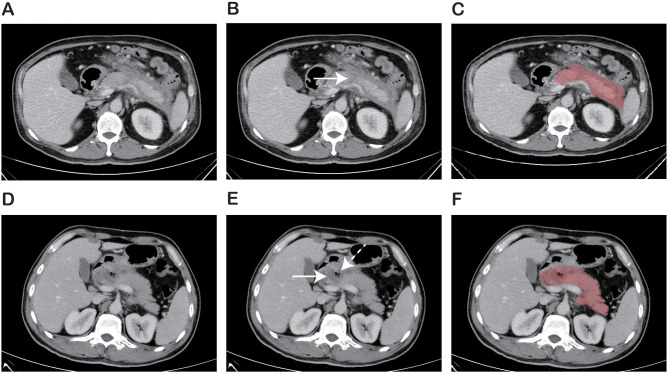

Purpose: This study aimed to establish a nomogram for early and accurate identification of infected pancreatic necrosis (IPN) among patients with acute necrotizing pancreatitis (ANP) by integrating clinical data and radiomic information from contrast-enhanced computed tomography (CECT).

Patients and methods: This retrospective single-center study included 203 ANP patients who underwent CECT. Patients were divided into training (n=142) and test set (n=61). Radiomic features were extracted from CECT images using PyRadiomics. Three machine learning classifiers were employed to construct a radiomic signature. Clinical factors were identified through regression analysis. A combined nomogram was developed using multivariate logistic regression. ROC and calibration curves were plotted to assess the efficacy of the model. Decision curve analysis (DCA) was applied to identify the clinical value and utility.